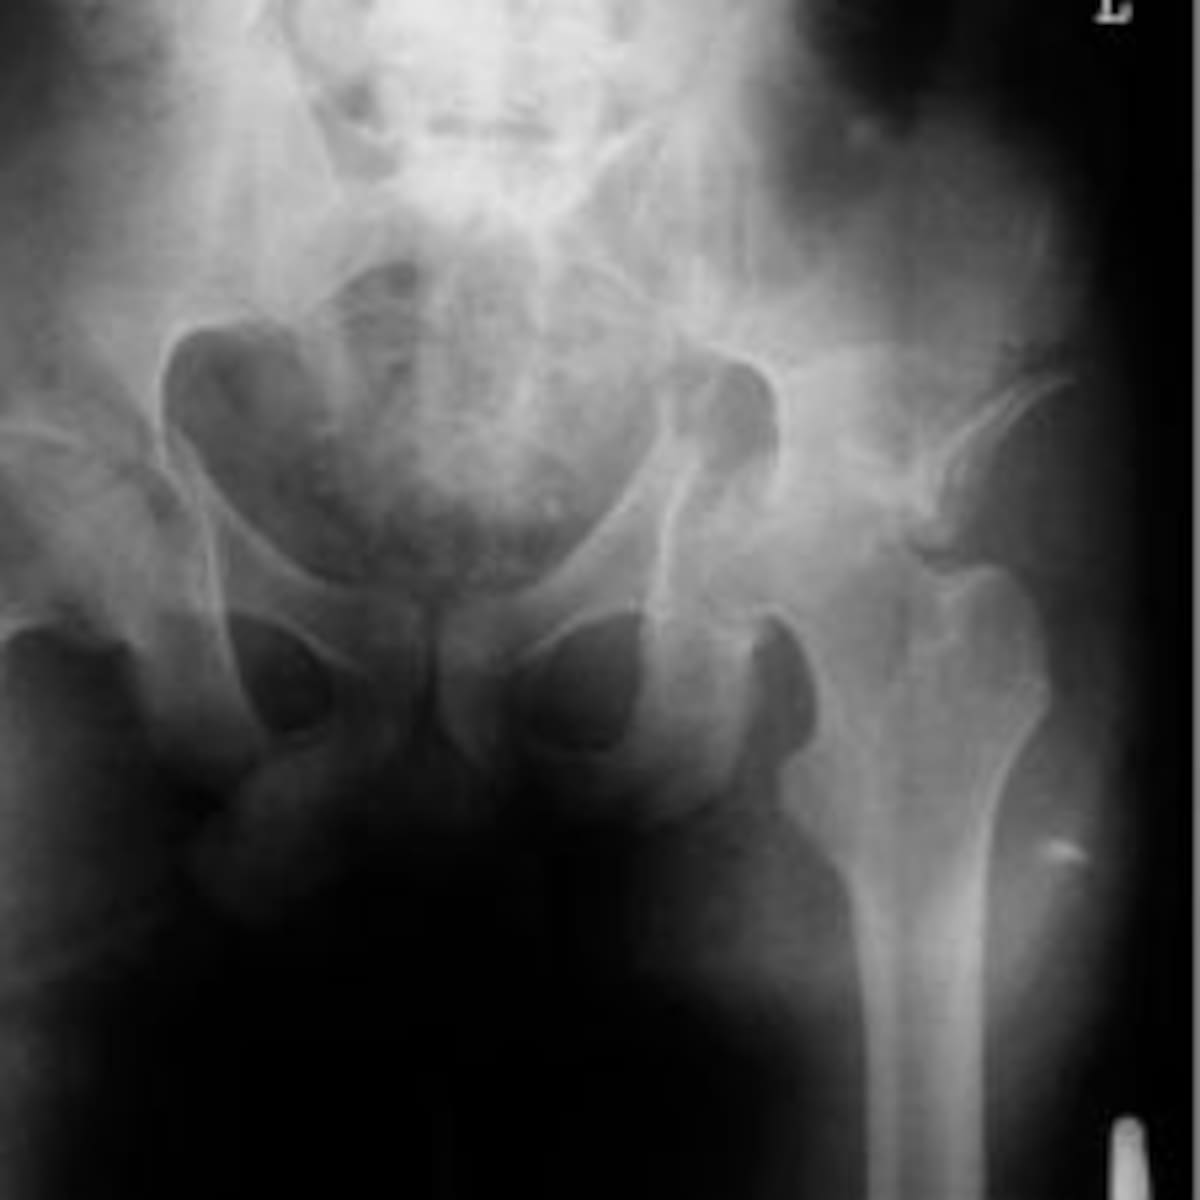

El milagro de Sebastián: Cae desde el piso 17 y solo se fractura la pelvis y el fémur

'Joven del milagro'

30/07/2015